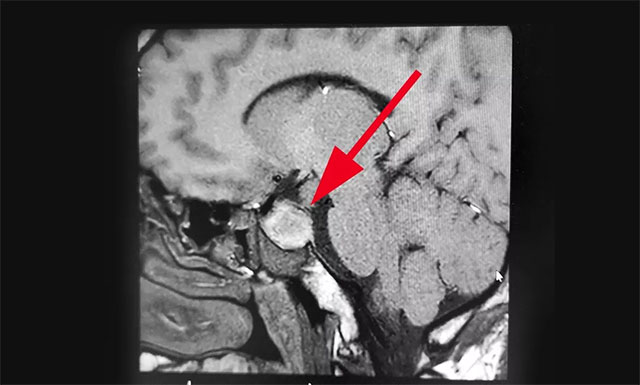

入院时,患者已经连续9天阵发性头痛,经检查其左侧眼睑有轻微下垂,约1米距离时有视物重影等症状,双眼视力0.2,四肢指关节较之前变粗大。针对患者情况,6B病区主任潘仁龙基于多年临床经验立即作出判断,急行头颅鞍区MRI平扫+增强,显示:蝶鞍显著扩大,鞍底下陷,鞍区见一不规则肿块,大小约1.6*3.2*2.1cm,病变向周围生长,突入鞍上池,推移视交叉,向下生长,鞍底受压,向鞍旁生长,海绵窦推挤改变。

▲ 术前影像:垂体大腺瘤,超蝶鞍生长,侵袭海绵窦

由潘仁龙主任、李士其教授、吴治群博士组成的专家组指出,根据患者影像学检查及检验结果分析,患者考虑为垂体大腺瘤伴卒中,患者面容有改变,怀疑为生长激素腺瘤。脑垂体瘤腺瘤出血,压迫了视网膜及海绵窦内的动眼神经,导致动眼神经麻痹,视物重影。